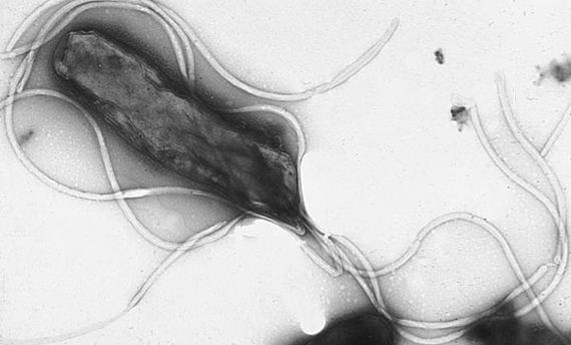

Se publica el consenso para optimizar el tratamiento de la bacteria 'Helicobacter pylori', que afecta a la mitad de la población española